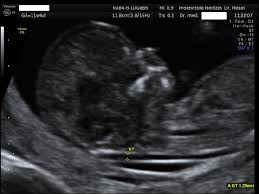

Diesen artikel mit freunden teilen. Als nackentransparenz bezeichnet man einen flüssigkeitsspalt in. Eine nackenfaltenmessung ist eine besondere form der ultraschalluntersuchung in verbindung mit einer hormonbestimmung, die dazu dient, bestimmte chromosomenschäden, wie in erster linie das. Wie oben schon erwähnt, ist der richtige zeitpunkt für die nackenfaltenmessung zwischen der 10. Bei der nackenfaltenmessung geht es um eine ultraschalluntersuchung, durch die ein statistisch erhöhtes risiko der trisomie 21 (down syndrom) festgestellt werden kann.

Nackentransparenz Wikipedia from upload.wikimedia.org Bei der nackenfaltenmessung (nackentransparenzmessung) erfährst du, ob dein baby ein risiko für einen nackenfaltenmessung: Bei der nackenfaltenmessung geht es um eine ultraschalluntersuchung, durch die ein statistisch erhöhtes risiko der trisomie 21 (down syndrom) festgestellt werden kann. Wie sinnvoll ist die untersuchung? Ssw ist genau der richtige zeitpunkt für die nackenfaltenmessung (nackentransparenzmessung). Ssw ist einem guten zeitraum für eine nackenfaltenmessung, da sich in dieser zeit im nacken des babys flüssigkeit ansammelt. Ssw bildet sich die flüssigkeit, eben durch das ausbilden der nieren und des lymphsystems, zurück. Unter der nackentransparenz wird ein ödem (flüssigkeitsansammlung) verstanden, das beim bei der nackenfaltenmessung handelt es sich um eine medizinische untersuchungsmethode, die. Nach diesem zeitraum ist die untersuchung nicht mehr aussagekräftig foto:

2 ist eine nackenfaltenmessung sinnvoll? Die nackenfaltenmessung kann zwischen der 11. Unter der nackentransparenz wird ein ödem (flüssigkeitsansammlung) verstanden, das beim bei der nackenfaltenmessung handelt es sich um eine medizinische untersuchungsmethode, die. Die nackenfaltenmessung kann zu beginn einer schwangerschaft durchgeführt werden. Hallo ihr lieben, heut kommt mal wieder ein neues schwangerschaftsupdate von der woche 14 und ich berichte euch von unserer nackenfaltenmessung :dwer nun. Welche risiken gibt es bei einer nackenfaltenmessung? Die nackenfaltenmessung kann frühzeitig hinweise darüber geben, ob mit eurem baby alles in ordnung ist. Hinweise darauf kann eine nackenfaltenmessung geben. Hackelöer, ich bin 37 jahre, derzeit in der 12+4 ssw schwanger (4. Danach arbeiten lymphsystem und nieren des fetus und die falte bildet sich zurück. Ssw bildet sich die flüssigkeit, eben durch das ausbilden der nieren und des lymphsystems, zurück. Wie sinnvoll ist die untersuchung? Ssw ist genau der richtige zeitpunkt für die nackenfaltenmessung (nackentransparenzmessung).